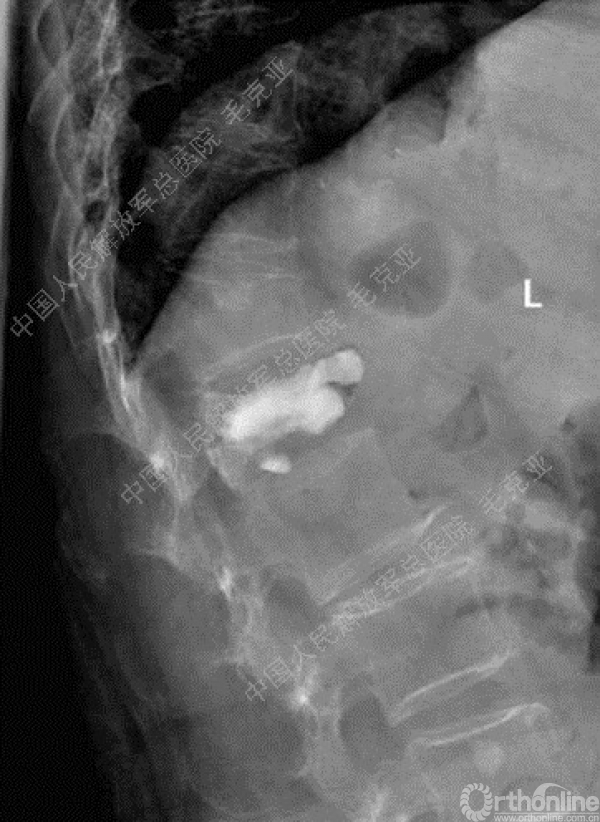

导语:随着社会老龄化的不断加速,骨质疏松性椎体压缩骨折作为一种普遍存在的老年骨科疾病已经成为现今骨科界的一个热点话题。传统的保守疗法治疗效果不佳,而现有的椎体增强技术又具有多种风险和缺陷。针对这种现状,中国人民解放军总医院毛克亚教授提供了一种新的解决方法。